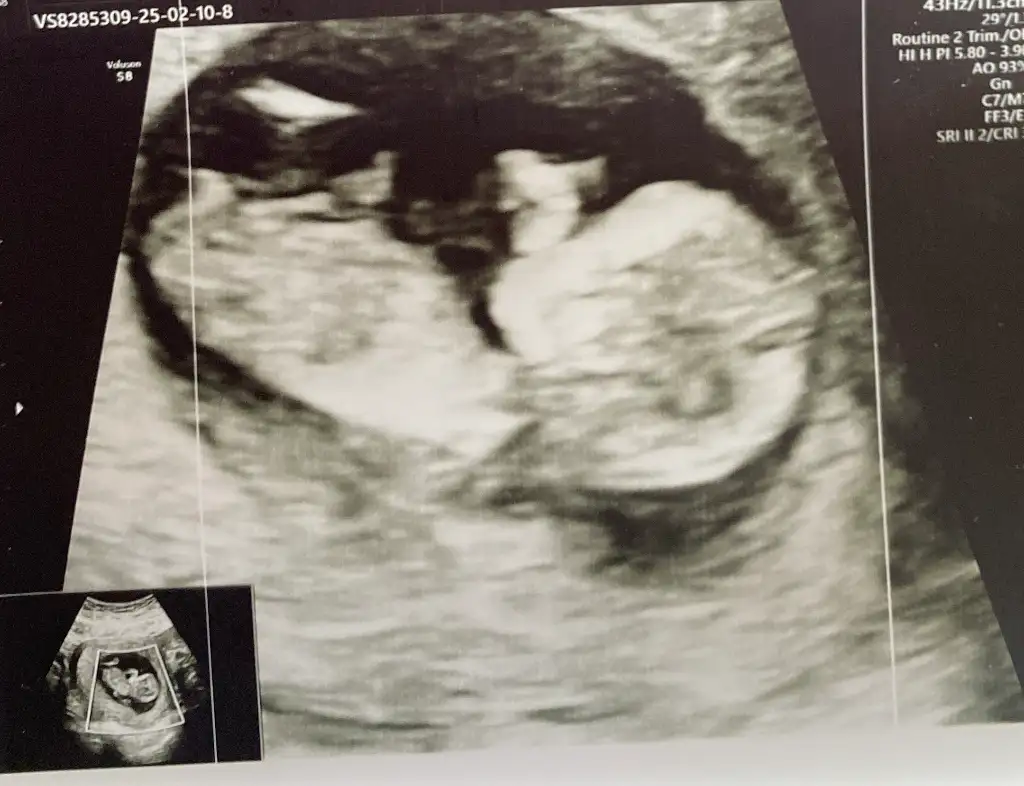

Sizce benimki ne anlıyor musunuz cinsiyetten çok merak ediyorum.Kızınız olcak ramzi teorisine göre nubu karşıya bakıyor benım görüşüme göre

my mister sen yorum yapıyordun dimi usg ye yardımcı olur musun

Cinsiyetiniz belli oldu muu, ben erkek gördüm sanki buradaSizce benimki ne anlıyor musunuz cinsiyetten çok merak ediyorum.